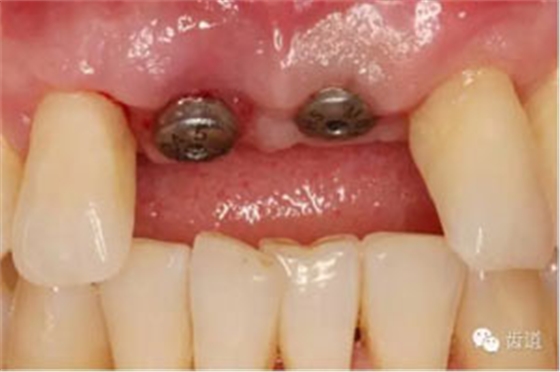

半年后復(fù)診

臨時(shí)冠塑形

合面觀